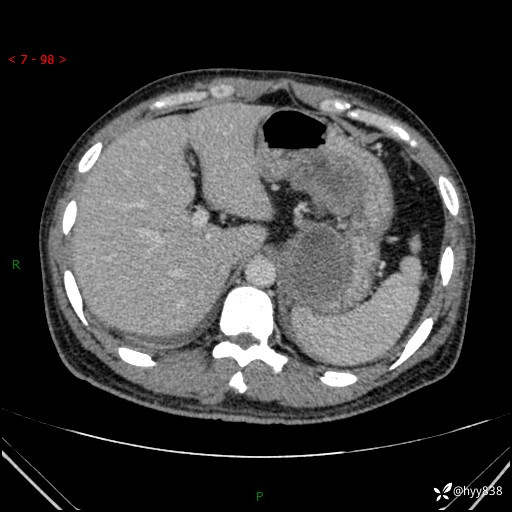

病例39岁/女,左侧腰痛入院。腹腔囊实性肿块,定位、定性---结果公布~

性别:男

年龄:39岁

简要病史:左侧腰痛待查,CT发现腹腔占位

腹部CT平扫+增强